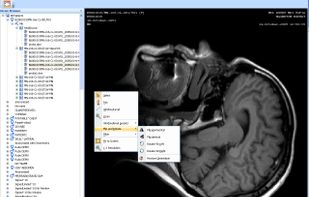

Free open source DICOM viewer for macOS, designed for 64-bit systems and based on OsiriX, offers advanced visualization, multimodal image fusion, measurement tools, image processing, PACS integration, file export, privacy features, and plugin support.